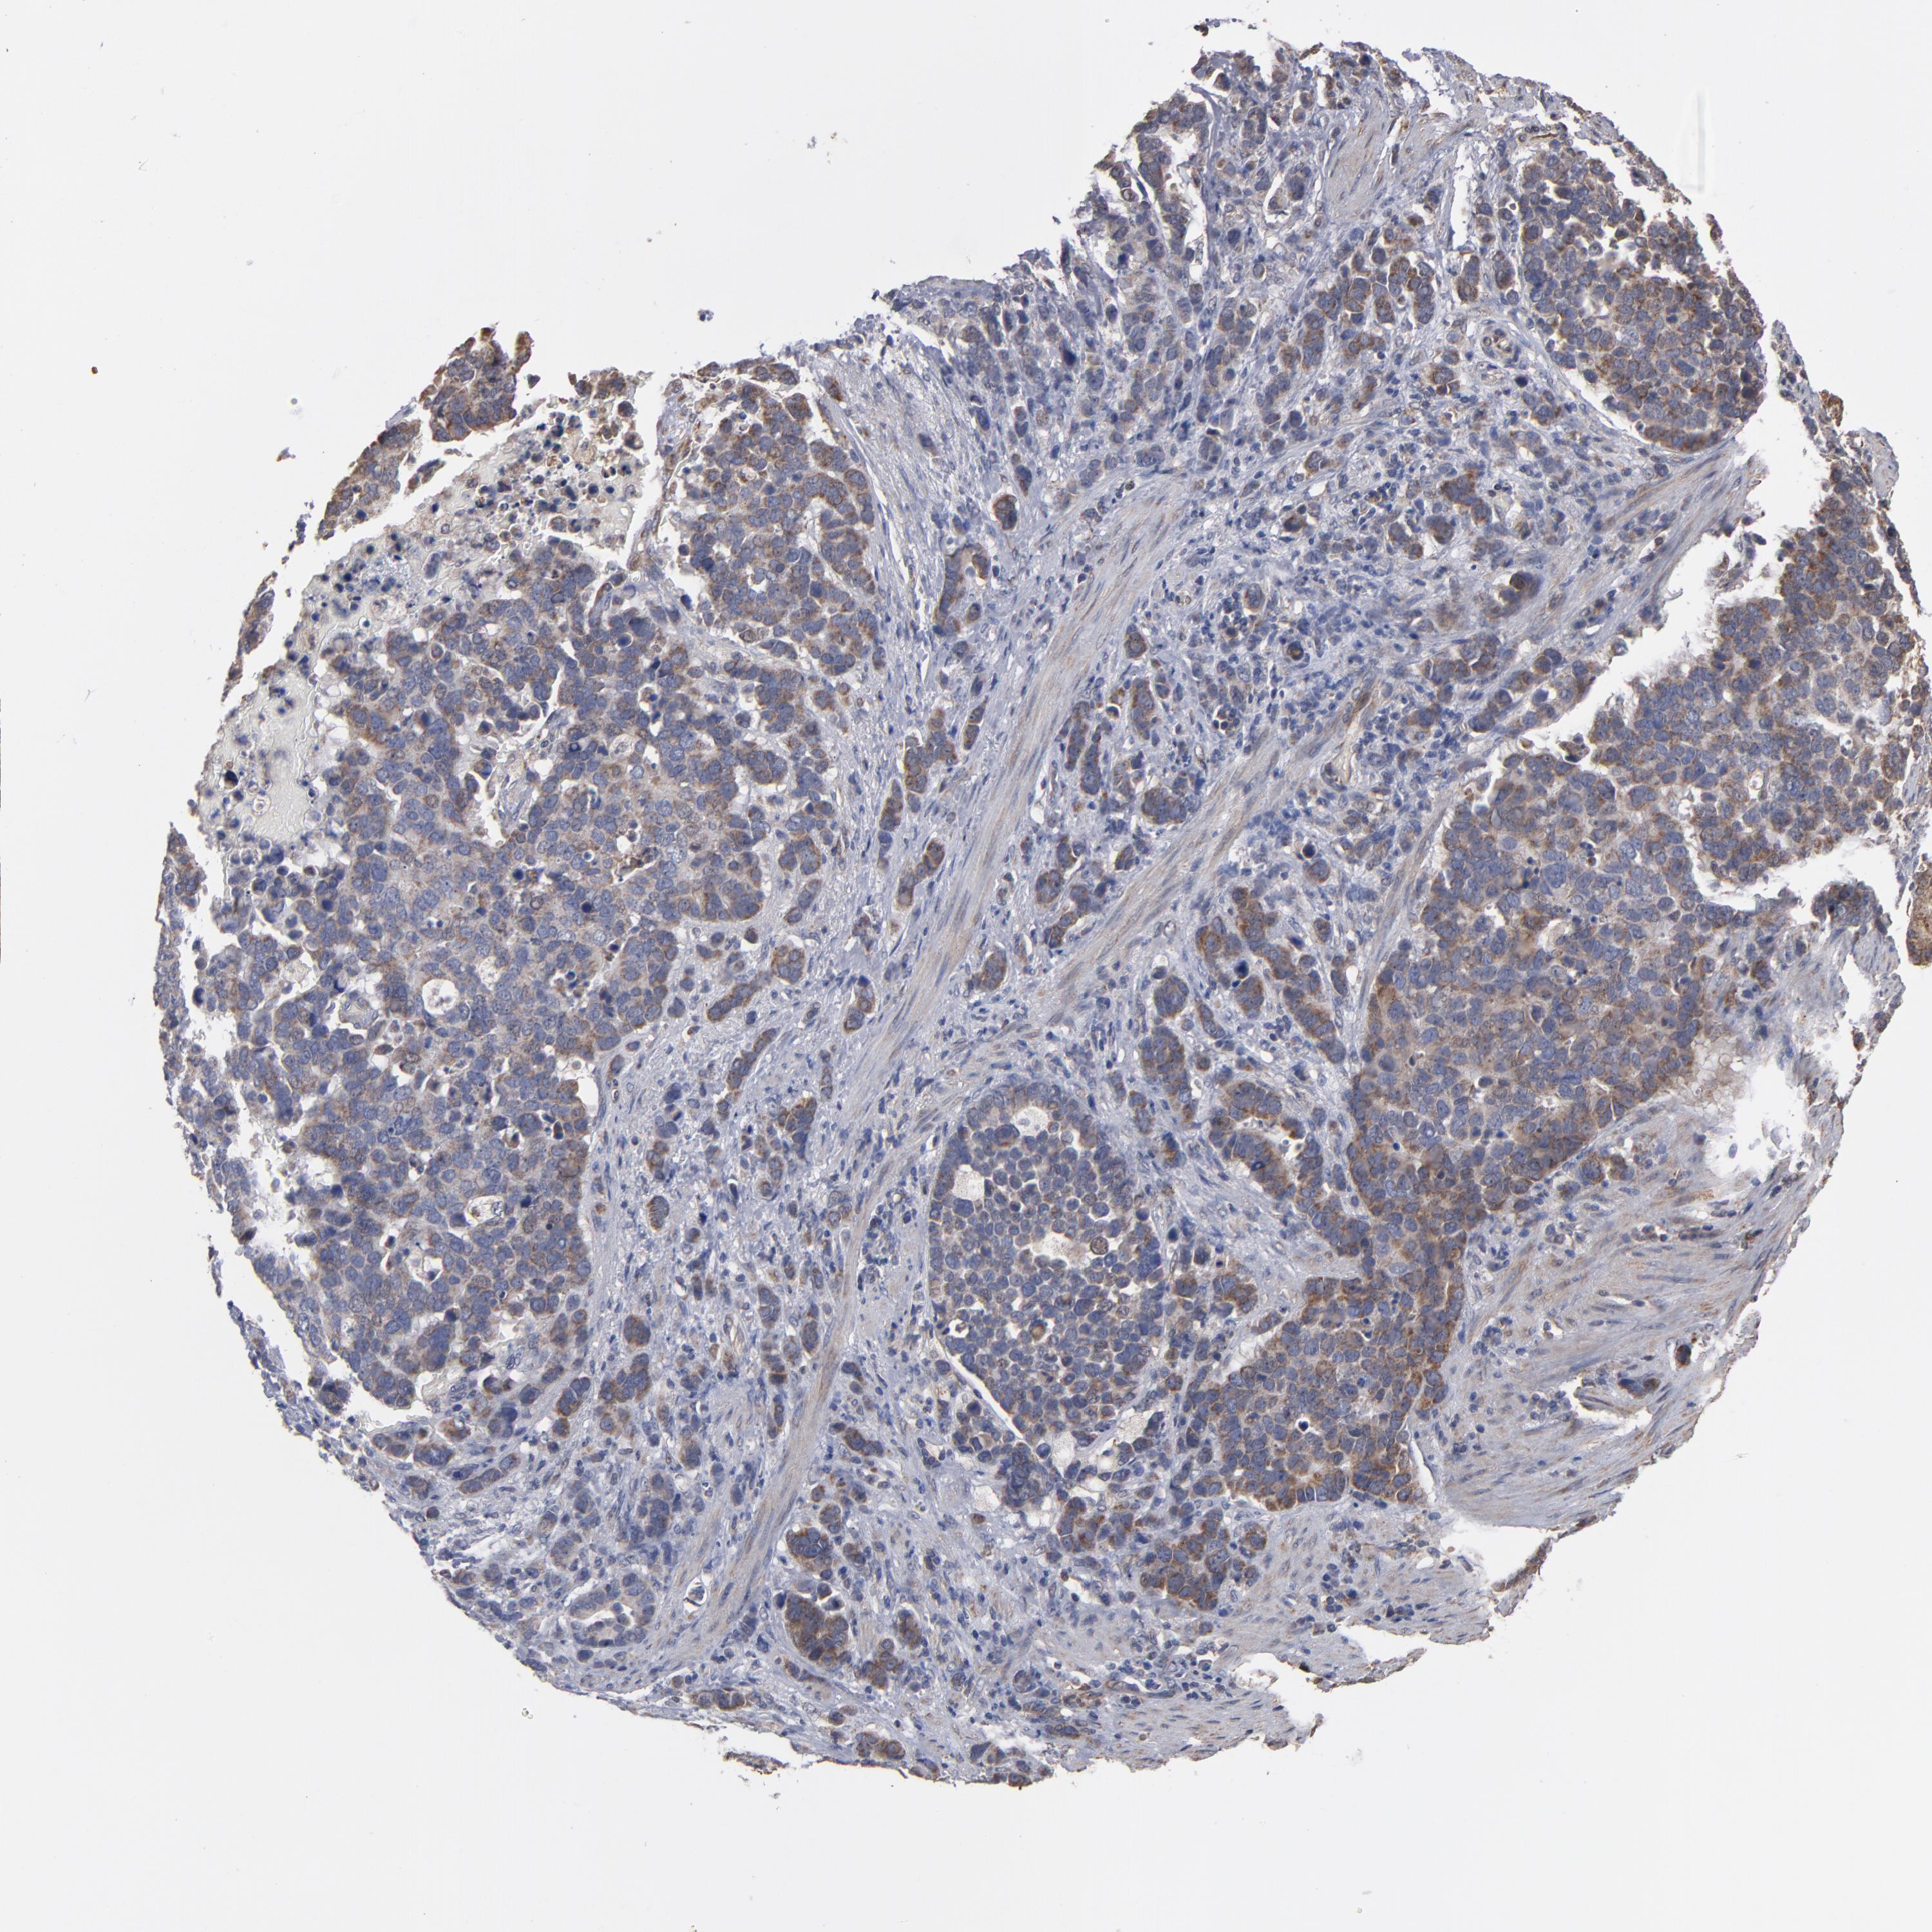

STOMACH CANCER - Protein expressioni

A mouse-over function shows sample information and annotation data. Click on an image to view it in a full screen mode. Samples can be filtered based on level of antibody staining by selecting one or several of the following categories: high, medium, low and not detected. The assay and annotation is described here.

Note that samples used for immunohistochemistry by the Human Protein Atlas do not correspond to samples in the TCGA dataset.

Antibody stainingi

Antibody staining in the annotated cell types in the current human tissue is reported as not detected, low, medium, or high, based on conventional immunohistochemistry profiling in selected tissues. This score is based on the combination of the staining intensity and fraction of stained cells.

Each image is clickable and will lead to virtual microscopy that enables deeper exploration of all samples and also displays staining intensity scores, fraction scores and subcellular localization as well as patient and tissue information for each sample.

Antibody HPA002893

Staining

High

Medium

Low

Not detected

Intensity

Strong

Moderate

Weak

Negative

Quantity

>75%

75%-25%

<25%

None

Location

Nuclear

Cytoplasmic/membranous

Cytoplasmic/membranous,nuclear

Adenocarcinoma, NOS